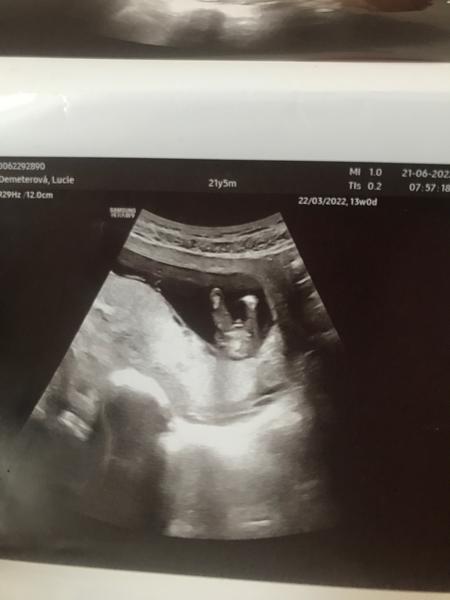

13. týden těhotenství. Lze z těchto fotek určit pohlaví?

Jsem teprve ve 13. tt a moc bych chtěla holčičku, ale myslím si, že je to kluk. Pan doktor mi to teď na prvním screenengu ještě nechtěl říct. Asi si nebyl jistý.🙂

bohužel nelze říci... ☹